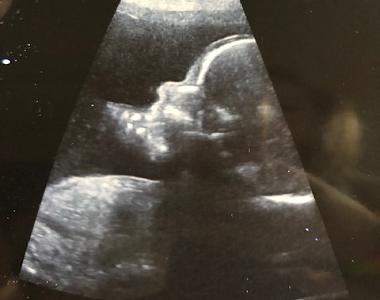

Přinášíme vám oblíbený seriál, ve kterém budeme sledovat náročné těhotenství maminky Katky doslova v přímém přenosu. Maminka Katka se s vámi podělí o své pocity, nálady, události aktuálních týdnů těhotenství. Nebudou chybět ani těhotenská vyšetření. Včetně jedinečného pohledu Katky na jejich rodinu, rodičovství jako partnerství a speciálně popíše i pohled chlapa na rodičovství. Tentokrát se máte opět na co těšit!